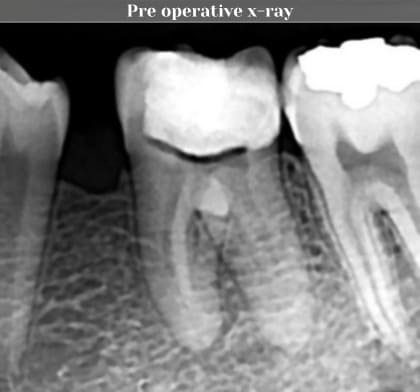

Pre operative x-ray